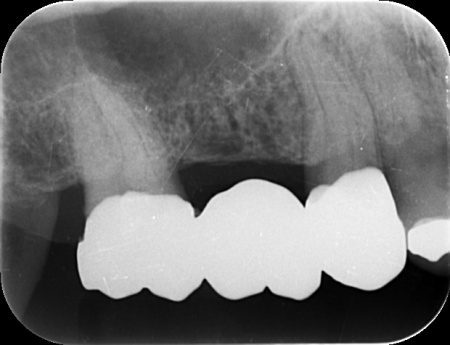

拝見したところ、右上の奥歯には複数の歯をつないだ被せ物であるブリッジが入っていましたが、被せ物の内部で虫歯が再発していました。

レントゲンを撮影して詳しく調べた結果、虫歯は比較的大きく歯の神経に近い深さまで進行していることが確認できました。

以上のことから、ブリッジを取り外して虫歯を治療する必要があると診断しました。

まずブリッジを慎重に取り外し、虫歯を確認します。